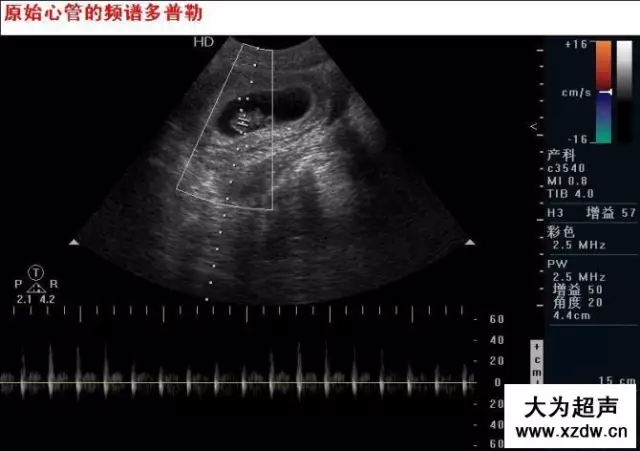

產(chǎn)科超聲正常圖片